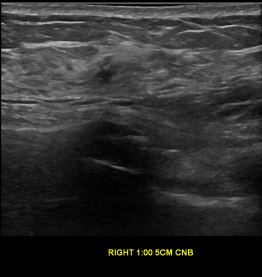

상기환자는 외부검사상 조직검사 권유받고 내원하신 60대 후반

여성분으로 의심스러운 우측유방혹 조직검사 시행해 제자리암으로 진단되었습니다